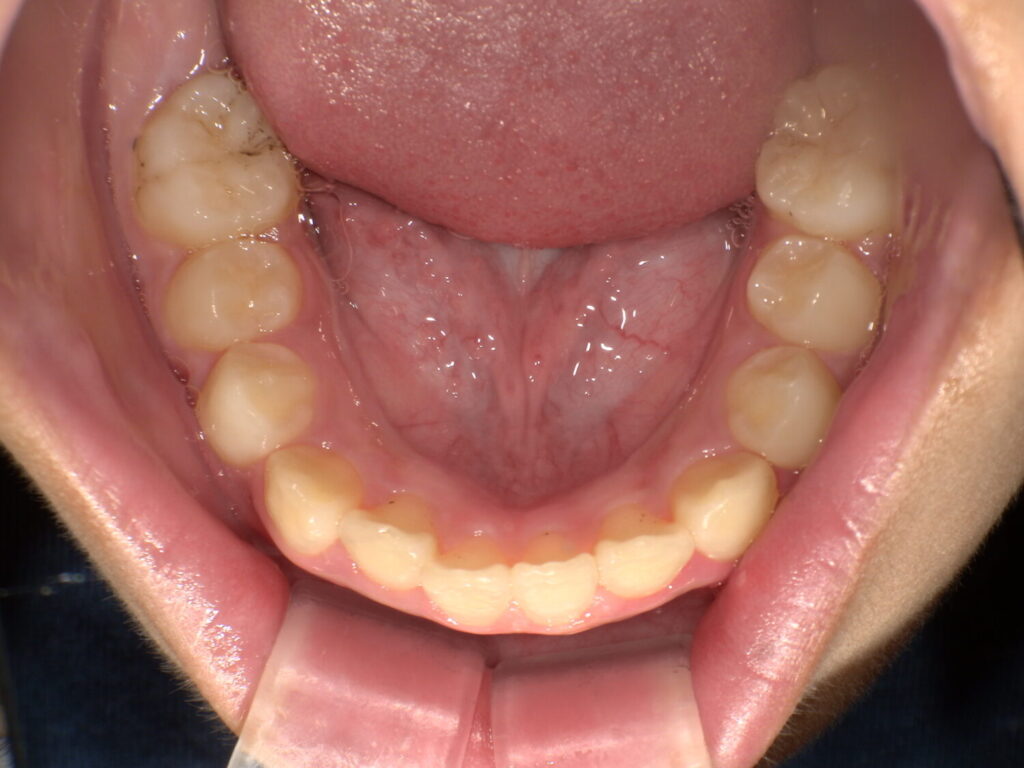

3番目の歯が抜けて生え変わる頃にグッと噛み合わせが変化して、下の歯も並びました。

マウスピースとアクティビティーでここまで変化しました!

また、前歯が大きいと言われていたことが気になっていましたが顎も大きくなって正しく並んでいると大きく感じなくなります。